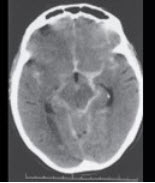

男性,23岁,突发剧烈头痛5小时入院,行头颅CT出现如图所示病变,应诊断为( )

A:脑出血

B:脑梗死

C:蛛网膜下隙出血

D:硬膜下出血

E:硬膜外出血